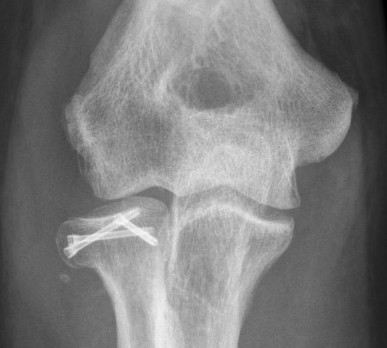

Radial head fragment nonunion

Overstuffing

| Lesser sigmoid notch | Symmetry of ulnohumeral joint |

|---|---|

|

Radial head shoulder articulate with lesser notch

Ensure no gapping of lateral ulnohumeral joint |

- cadaveric study

- increased medial ulno-humeral joint line gapping with overlengthening of 6 or 8 mm

- increased lateral ulno-humeral joint line gapping with overlengthening of 2 mm